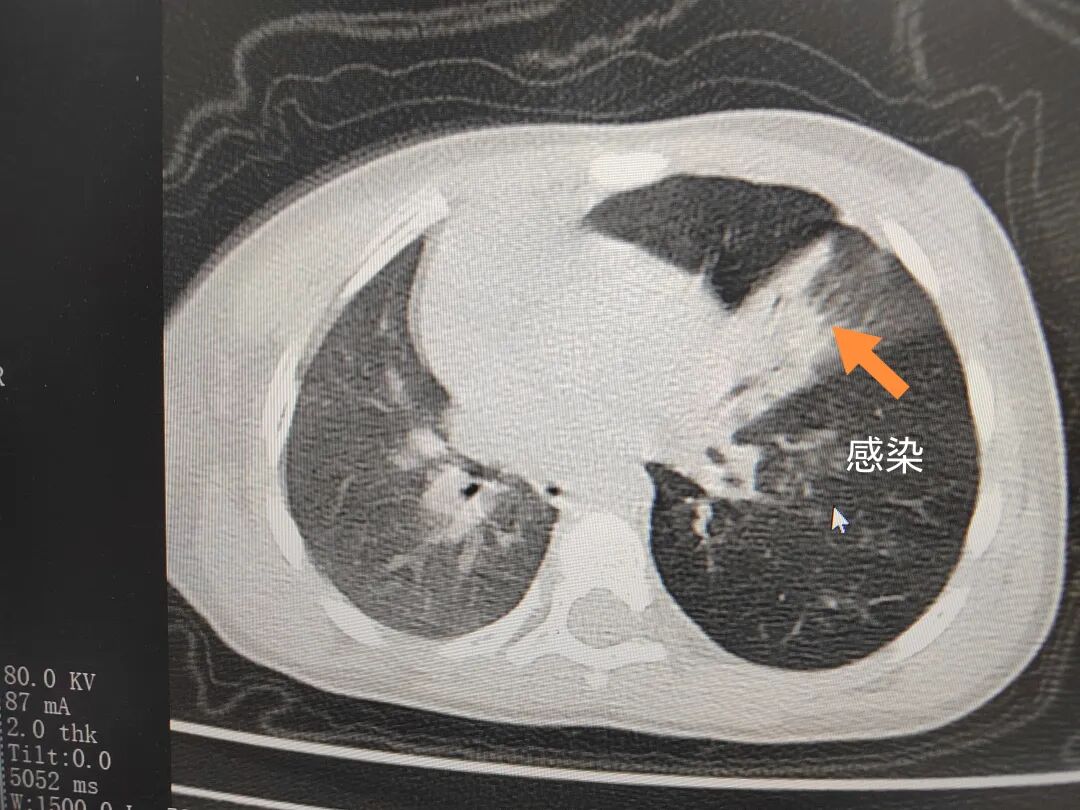

三天后(11月13日),趙寶出現(xiàn)高熱、咳喘加重,家長著急了,再次帶他來到醫(yī)院。CT檢查顯示左肺過度充氣,左肺上下葉支氣管主干見不規(guī)則高密度影,左肺上葉可見大片狀密度增高影,縱隔窗實變,提示為“左側(cè)支氣管內(nèi)異物并繼發(fā)性改變,左肺上葉舌段肺膨脹不全”。

市二院小兒呼吸內(nèi)科團隊迅速為患兒制定了周密的手術(shù)方案,并很快安排了氣管鏡探查。術(shù)中,主治醫(yī)師田慧等憑借嫻熟的氣管鏡操作技術(shù)成功將異物大塊板栗取出。由于板栗在氣管內(nèi)存留時間較長,質(zhì)地軟糯易碎,大大增加了手術(shù)難度。檢查還發(fā)現(xiàn),異物停留部位的氣管黏膜已出現(xiàn)充血紅腫、糜爛,導(dǎo)致患兒住院時間相應(yīng)延長。此次事件給趙寶的家庭帶來了不小的驚嚇與擔(dān)憂,也再次為廣大家長敲響了警鐘。

市二院小兒呼吸內(nèi)科副主任楊亞娟介紹,異物誤入氣道可能導(dǎo)致氣道阻塞,嚴(yán)重時可引發(fā)窒息,甚至危及生命。若異物進入支氣管,造成不完全堵塞,可引起阻塞性肺氣腫;如完全堵塞支氣管,則可能導(dǎo)致肺組織萎縮,形成肺不張。此外,若異物存留時間較長,或為植物性異物,容易合并細(xì)菌感染,產(chǎn)生膿性分泌物,進而發(fā)展為肺炎。她強調(diào),盡早診斷并取出異物,是減少并發(fā)癥、降低病死率的關(guān)鍵。